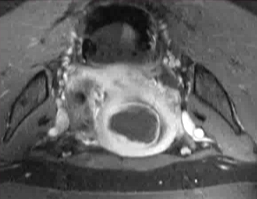

在开始该程序之前,会先进行手动分割操作。 随后,一款专用软件会自动制定出最佳的治疗方案。

在操作过程中,会进行多次超声波治疗,直至覆盖住足够的子宫肌瘤体积。 每次超声处理持续 20 至 40 秒,每次超声处理之间会有冷却时间(最长可达 90 秒)。 磁共振成像技术中质子共振频率的偏移特性使得能够监测每一个治疗点的温度。

经过治疗后,会进行核磁增强以评估被切除区域的范围。